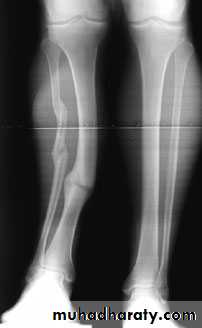

FRACTURES OF TIBIA AND FIBULA

Mechanism of injury1-Indirect injury is usually low energy; with a spiral or long oblique fracture one of the bone fragments may pierce the skin from within.

2-Direct injury crushes or splits the skin over the fracture; this is usually a high-energy injury and the most common cause is a motorcycle accident.

The limb should be carefully examined for signs of soft-tissue damage: bruising, severe swelling, crushing or tenting of the skin, an open wound, circulatory changes, weak or absent pulses, diminution or loss of sensation and inability to move the toes. Any deformity should be noted before splinting the limb. Always be on the alert for signs of an impending compartment syndrome.X-ray

The entire length of the tibia and fibula, as well as the knee and ankle joints, must be seen. The type of fracture, its level and the degree of angulation and displacement are recorded Spiral fractures without comminution are low energy injuries. Transverse, short oblique and comminuted fractures, especially if displaced or associated with a fibular fracture at a similar level, are high energy injuries.Management